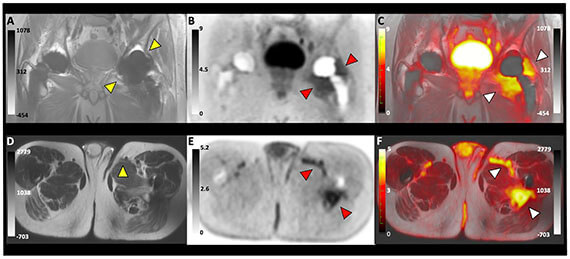

- Qin H, Zhang V, Bob R, Delos Santos R, Cunha A, Hsu I, Delos Santos J, Lee J, Subramaniam S, Larson P, Vigneron D, Wilson DM* , Sriram R*, Kurhanewicz K*. Simultaneous metabolic and perfusion imaging using hyper polarized 13C MRI can evaluate early and dose-dependent responses to prostate cancer radiotherapy (2020). The International Journal of Radiation Oncology, Biology, and Physics 107(5): 887-896.

The Wilson laboratory is pursuing clinically translatable biomarkers for infection, particularly discitis-osteomyelitis, which may be difficult to diagnose using computed tomography (CT) and magnetic resonance imaging (MRI). Existing clinical strategies to image bacterial infection in patients rely on activated immune cells (either 111In white blood-cell scan or 18F-FDG) and thus cannot reliably distinguish living bacteria from sterile inflammation. We are studying translational biomarkers for hyperpolarized 13C spectroscopy and positron emission tomography (PET) that target metabolic pathways specific to bacteria. We have developed several agents with excellent clinical promise including D-amino acid derived tracers (collaborative work with co-PI’s Michael Ohliger and Oren Rosenberg). More recently we have developed imaging tools to detect the suppression of ACE2, the primary receptor for SARS-CoV-2 entry, in COVID-19.